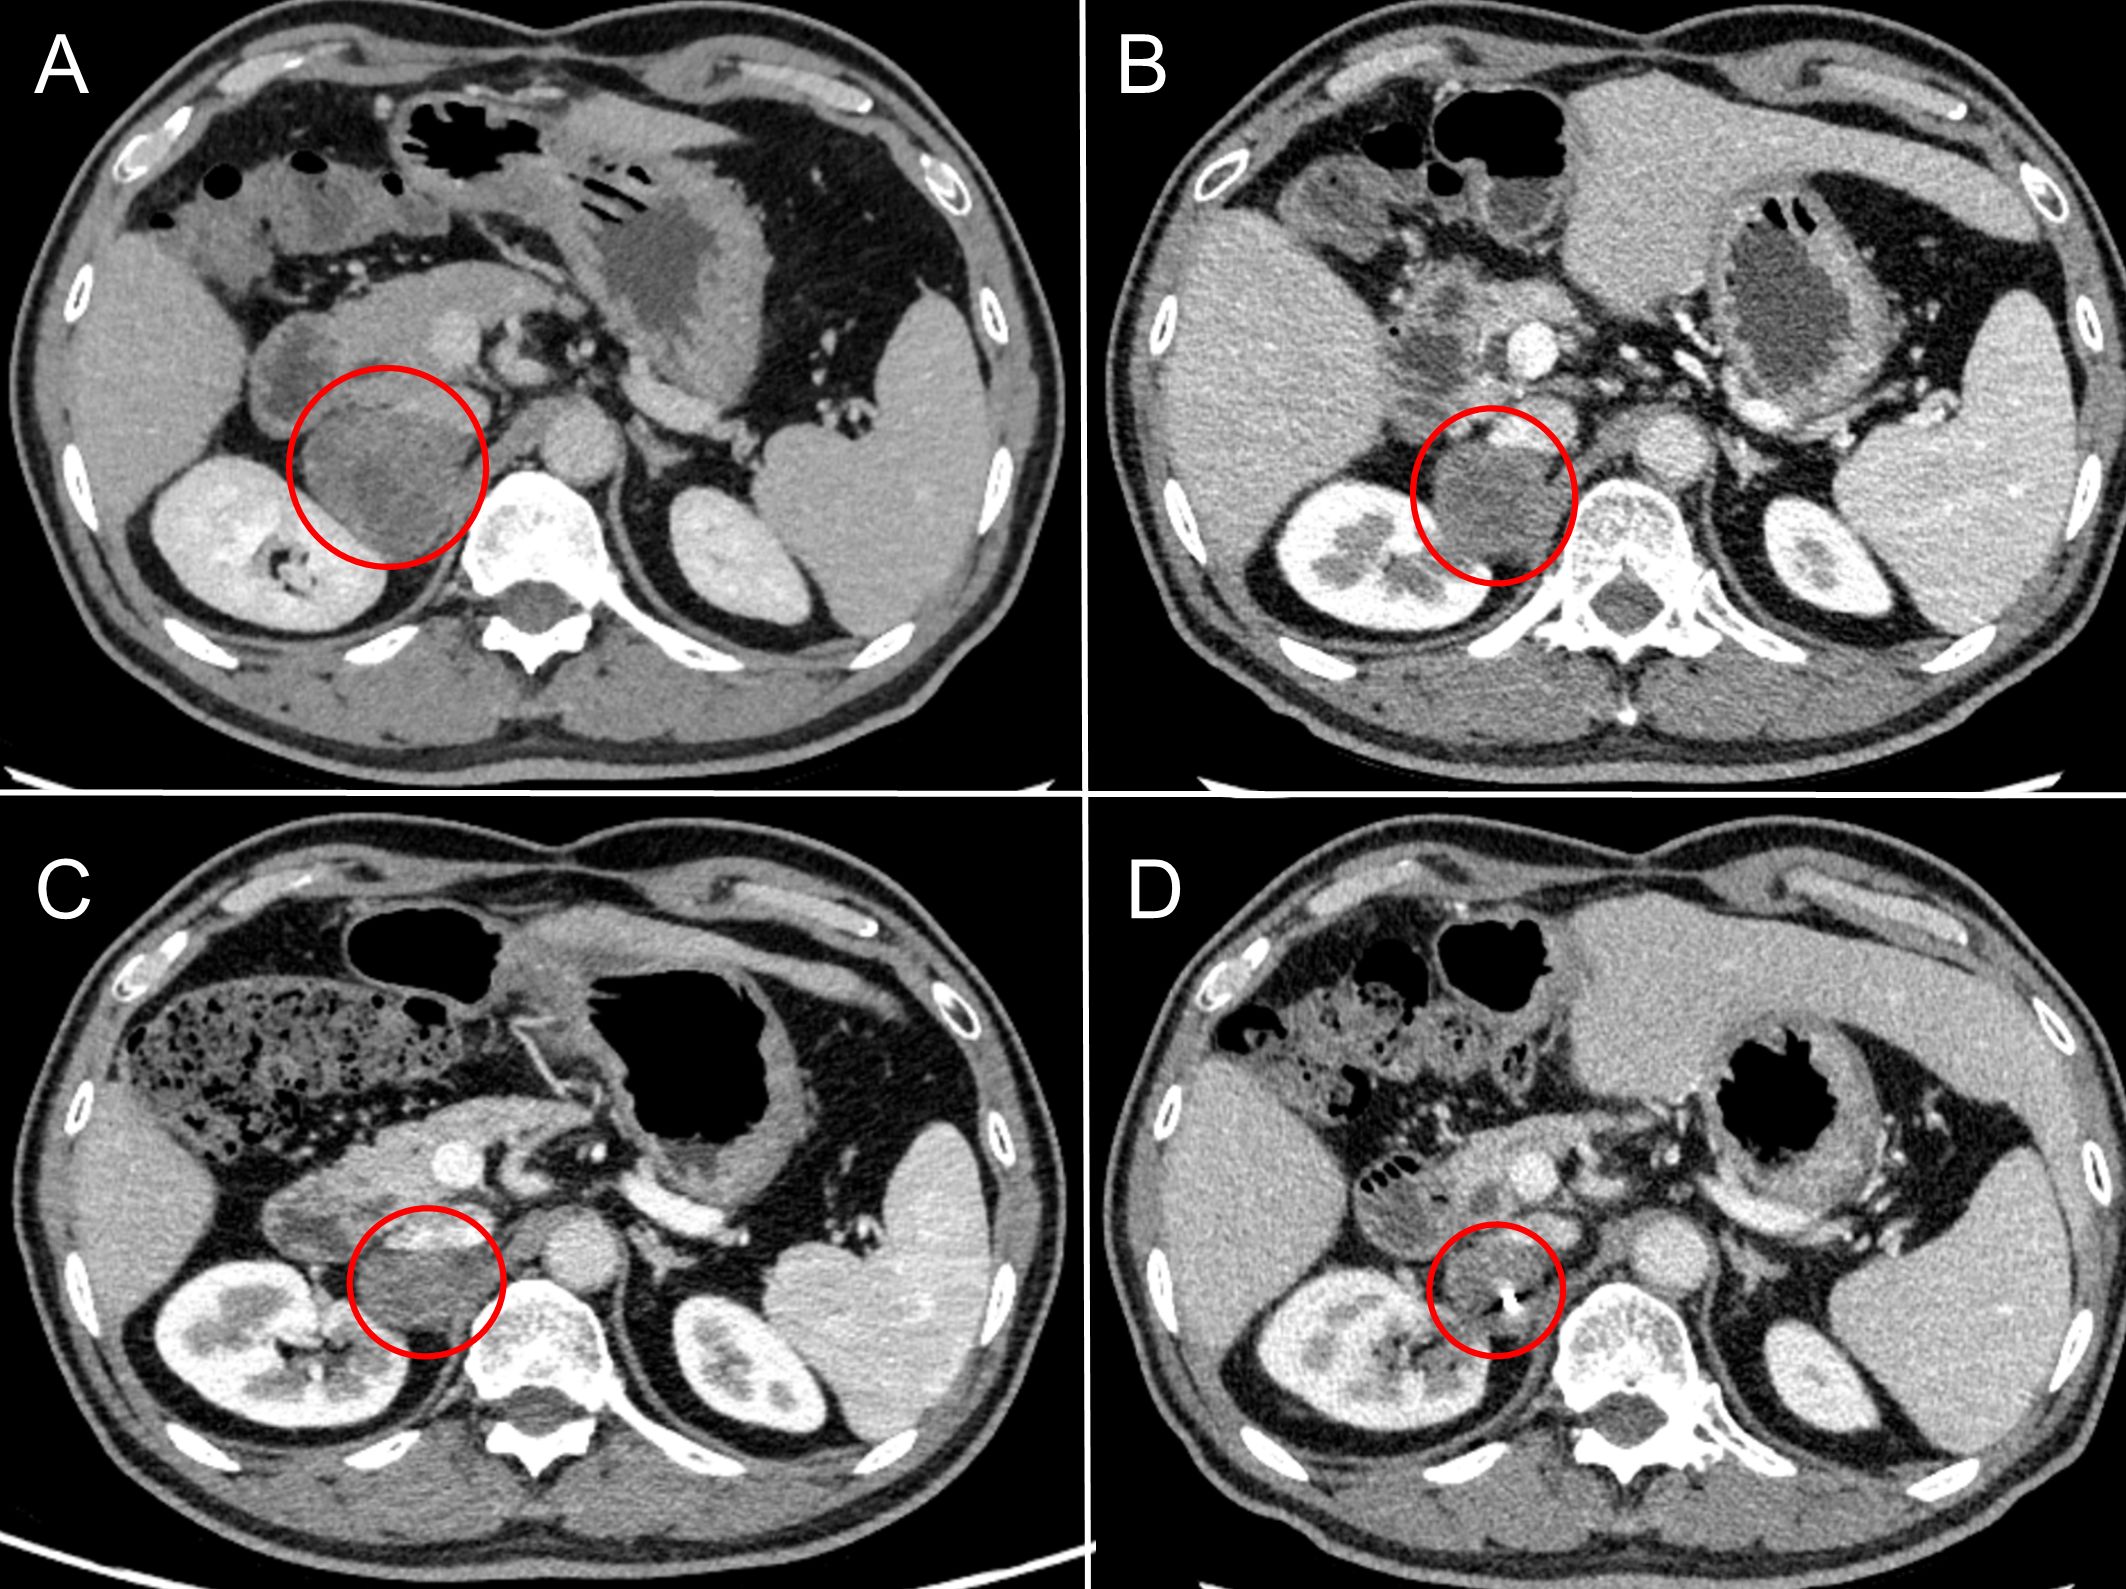

In March 2019, a second hepatectomy was performed due to hepatic recurrence, followed by four cycles of GP (gemcitabine and cisplatin) regimen chemotherapy (Figure 1B). Due to right adrenal metastasis, progressive disease (PD) occurred after only two cycles of AS (albumin-bound paclitaxel and S-1) regimen chemotherapy (Figure 2A). Next-generation sequencing (NGS) tests (Nanjing Geneseeq Technology Inc.) showed revealed ERBB2 amplification (7.4-fold) (Figure 1C). From May 2020 to August 2021, dual HER2-targeted therapy with trastuzumab (6 mg/kg every three weeks) and pyrotinib (400 mg daily) achieved the disease control for 18 months, during which cryoablation and pathological biopsy were conducted on the right adrenal lesion (Figure 2B). Due to PD in the right adrenal lesions, the patient enrolled in a phase I trial of DP303c (a HER2-targeted ADC). After two cycles, the efficacy was evaluated as stable disease (SD), but the patient withdrew after three cycles due to fatigue. The right adrenal gland was treated with CyberKnife radiosurgery in January 2022 (Figure 2C) and odine-125 seed implantation was performed in March 2023 due to PD in the right adrenal lesion (Figure 2D). The combination immunotherapy with lenvatinib (12 mg/day) plus pembrolizumab (200 mg q3w) was initiated for new lung metastases, resulting in SD. However, pembrolizumab was discontinued after two cycles due to grade 2 interstitial pneumonitis. Lenvatinib monotherapy has since maintained SD to date. The tumor marker CA199 in this patient closely mirrored the therapeutic effect, showing a significant decline following effective treatment (Figure 3). At the last follow-up in March 2025, the patient had achieved an OS of 90 months (Figure 4).

Figure 2

CT scan images showing abdominal cross-sections labeled A, B, C, and D. Each section has a red circle highlighting a specific area of interest, suggesting a consistent point of examination across all four images.

Figure 2. Radiographic changes in adrenal metastases under sequential local interventions. (A) Pre-treatment baseline (March 2020): CT scan revealing a new right adrenal metastasis. (B) After cryoablation (February 2021): CT image post-cryoablation shows a reduction in lesion size and density, indicating successful local tumor control. (C) After CyberKnife radiosurgery (February 2022): CT image demonstrates well-defined radiation-induced changes surrounding the lesion. (D) After odine-125 seed implantation (March 2023): CT image confirming the precise intra-tumoral placement of radioactive seeds.